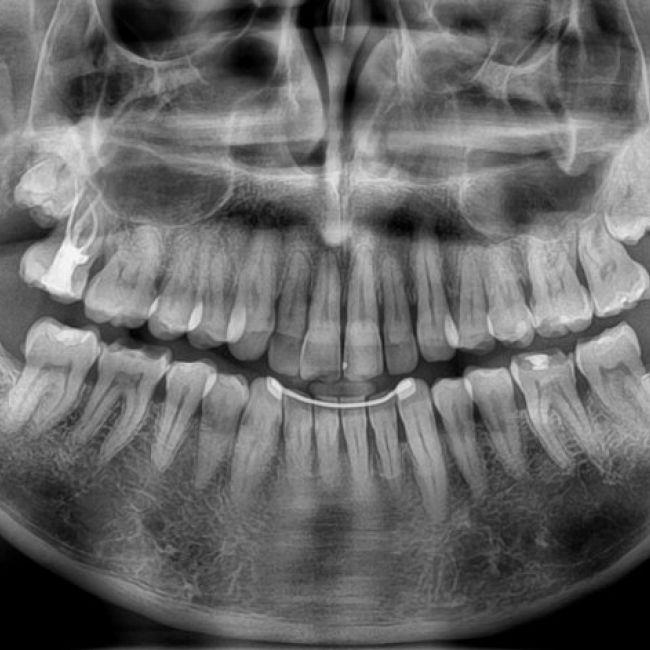

En los centros de Imagen Diagnóstica Dental Dr. Mayor ofrecemos una amplia variedad de servicios, gracias a la moderna aparatología con las que contanmos. Las pruebas diagnósticas que realizamos en nuestro centro son las siguientes:

“Excelente centro de radiodiagnóstico con grandes profesionales. Como especialista en Ortodoncia quiero destacar los estudios previos al inicio del tratamiento: fotografías extra e intraorales, radiografías, cefalometrías,etc. Los pacientes me comentan el magnífico trato recibido y la puntualidad.”